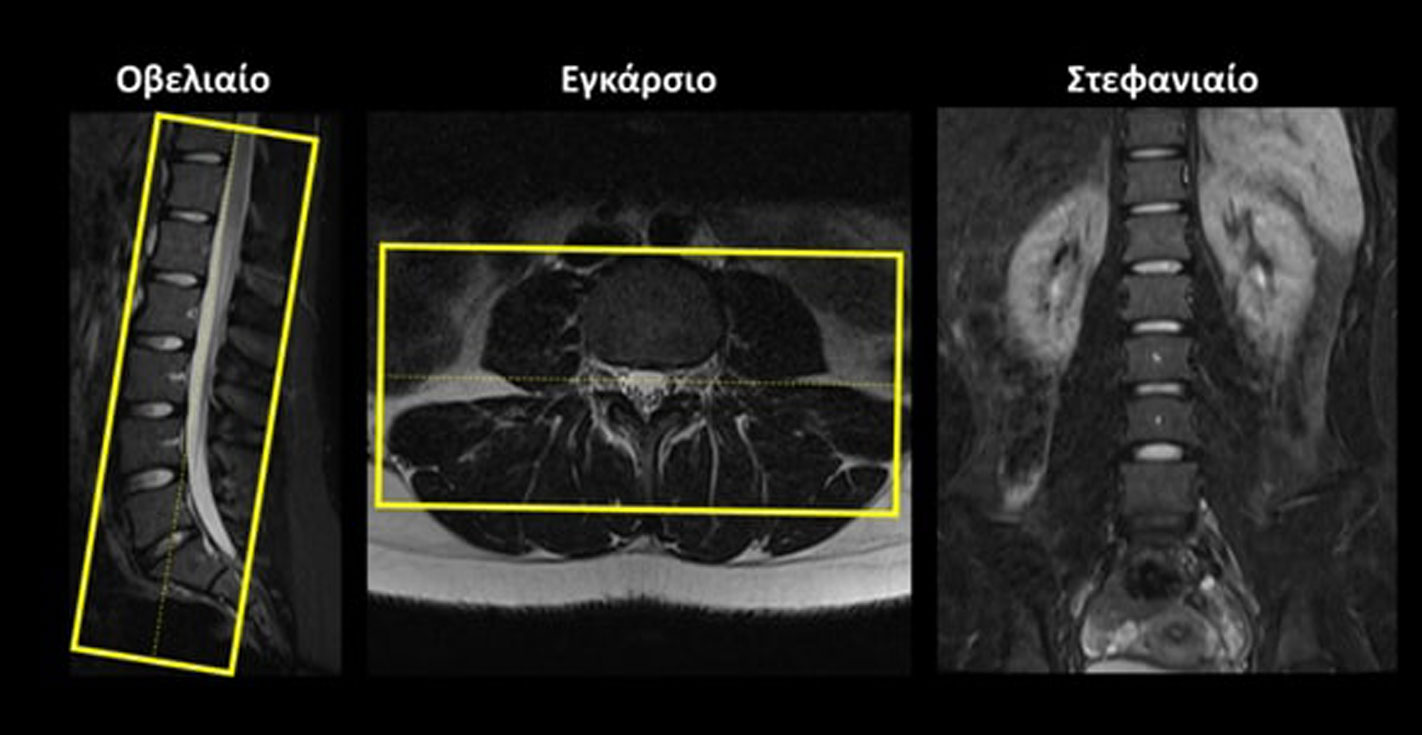

Σχεδιασμός τομών

Οβελιαίο (Sagittal): οι οβελιαίες τομές σχεδιάζονται παράλληλα με τους 5 οσφυϊκούς σπονδύλους στο στεφανιαίο επίπεδο και παράλληλα με την νοητή γραμμή που ενώνει το σπονδυλικό σώμα και την ακανθώδη απόφυση στο εγκάρσιο επίπεδο. Οι τομές πρέπει να περιλαμβάνουν ολόκληρα τα σπονδυλικά σώματα από τα δεξιά έως τα αριστερά.

Στεφανιαίο (Coronal): οι στεφανιαίες τομές σχεδιάζονται παράλληλα με το σπονδυλικό κανάλι στο οβελιαίο επίπεδο και κάθετα στην νοητή γραμμή που ενώνει το σπονδυλικό σώμα και την ακανθώδη απόφυση στο εγκάρσιο επίπεδο. Οι τομές πρέπει να περιλαμβάνουν ολόκληρα τα σπονδυλικά σώματα και το σπονδυλικό κανάλι από μπροστά μέχρι πίσω.

Εγκάρσιο (Axial/Transversal): οι εγκάρσιες τομές συνήθως λαμβάνονται ως 5 ξεχωριστά πακέτα και σχεδιάζονται παράλληλα με τον κάθε έναν μεσοσπονδύλιο δίσκο, τόσο στο οβελιαίο όσο και στο στεφανιαίο επίπεδο. Οι τομές πρέπει να περιλαμβάνουν ολόκληρους τους μεσοσπονδυλίους δίσκους από πάνω έως κάτω.